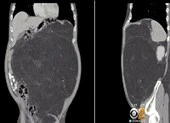

Ngày 22-5, thông tin từ bệnh viện K cơ sở Tân Triều, Hà Nội cho biết các bác sĩ khoa Ngoại Bụng 1 của bệnh viện vừa phẫu thuật thành công, lấy khối u mạc treo nặng 10 kg trong ổ bụng bệnh nhân CVT, 46 tuổi, Sơn Tây, Hà Nội.

Trước đó, bệnh nhân T. đến Bệnh viện K khám trong tình trạng bị đau bụng kéo dài hơn sáu tháng, luôn đầy bụng khó tiêu. Sau khi thăm khám, kiểm tra, các bác sĩ phát hiện trong bụng bệnh nhân có khối u lớn chiếm nửa bụng trái và phần giữa ổ bụng, cần phải phẫu thuật loại bỏ. Nếu không phẫu thuật kịp sẽ ảnh hưởng nghiêm trọng đến sức khỏe bệnh nhân do khối u kích thước lớn, xâm lấn vào đại tràng và niệu quản trái.

Ngày 14-5, sau 5 giờ phẫu thuật, êkíp phẫu thuật đã lấy toàn bộ khối u 10 kg ra khỏi ổ bụng bệnh nhân. Cắt đoạn đại tràng trái và đại tràng sigma, cắt đoạn niệu quản trái, nối lại niệu quản trái bảo tồn thận trái, lách, các mạch máu lớn.